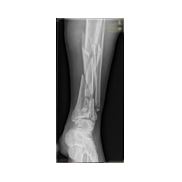

Görüntüleri büyütmek için resmin üstüne tıklayınız.